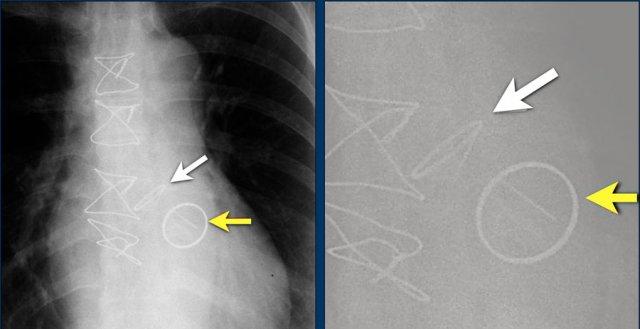

Hội chứng Twiddler

Hội chứng Twiddler là tình trạng máy tạo nhịp tim hoạt động không bình thường do bệnh nhân tự tác động vào thiết bị, dẫn đến lệch vị trí các điện cực.

Hậu quả là máy tạo nhịp hoạt động sai chức năng hoặc đôi khi kích thích các cấu trúc khác như thần kinh hoành hoặc đám rối thần kinh cánh tay.

Hình ảnh bên trái cho thấy bệnh nhân có ICD được đặt đúng vị trí.

Vài tháng sau, thiết bị hoạt động không bình thường do hộp ICD và điện cực bị xoay (mũi tên vàng) và co rút lại (mũi tên trắng).

Đây là một bệnh nhân khác mắc hội chứng Twiddler.

Lưu ý hình ảnh điện cực bị cuộn xoắn gần máy tạo nhịp và tại đầu điện cực trong thất phải (mũi tên).